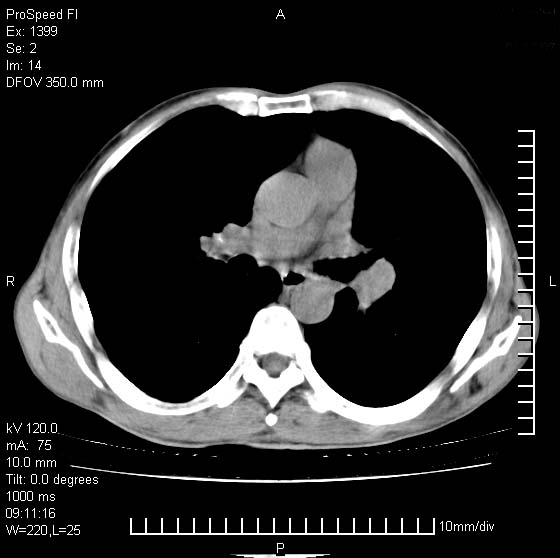

以下是引用rgsyyf在2007-1-19 11:05:00的发言:[br]左肺上叶见形态不规则巨大软组织肿块影,边缘呈分叶征,纵隔内隆突下见肿大淋巴结,右肺内另见一不规则结节影 .考虑:左肺周围性肺癌伴纵隔即右肺内转移.